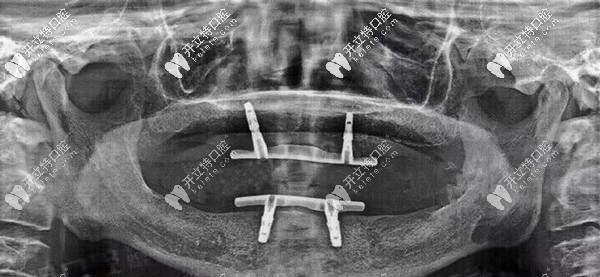

經(jīng)過一系列口腔拍片檢查后,陳叔口腔適合立得用技術(shù)做全口種植,當(dāng)時就和家人一起跟醫(yī)生確定了方案以及種植時間。